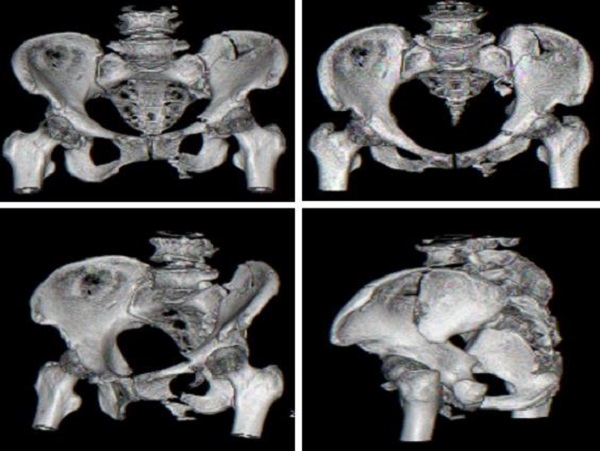

术前CT检查:

术前,创伤骨科郭永良主任医师团队应用MIMICS软件重建患者骨盆LC—II通道螺钉方向和长度,术中郭永良主任亲自主刀,使用Schanz针协助闭合复位,结合术前模拟通道螺钉方向精确制导,以最小的创伤将LC-Ⅱ通道螺钉顺利置入合适位置,而且完美避开神经及血管损伤,仅通过3枚螺钉使骨盆LC—II型骨折得到有效的稳定固定。